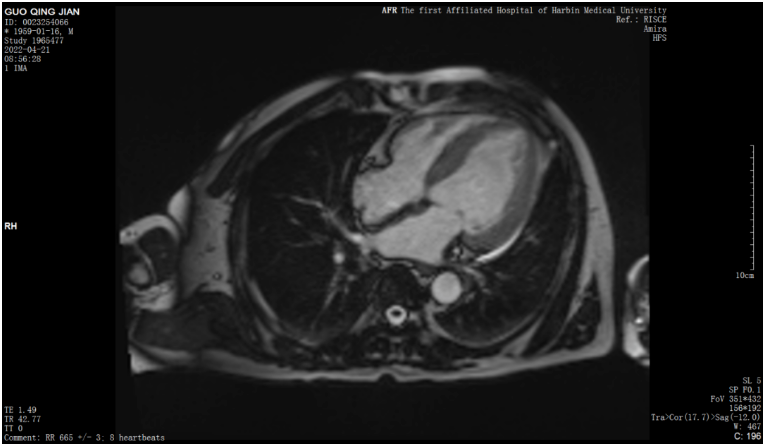

心脏磁共振

4.心脏磁共振 (CMR)在CA的诊断中的作用

CMR不仅可以评价心脏的结构和功能,还可以显示心肌的组织学特征,79%的ATTR患者存在非对称性室间隔肥厚,18%的患者为对称性LVH,还有3%的患者左心室几何结构正常 ,常合并右心室肥厚,心肌钆对比剂典型的“淀粉样LGE模式”是广泛的心内膜下LGE,不符合冠状动脉供血的区域分布。也可以表现为弥漫性透壁或心肌内片状LGE。心内膜下LGE常见于AL,透壁LGE常见于ATTRLGE比超声心动图和CMR功能评估特异度和敏感度更。但CMR不能准确区分AL和ATTR。